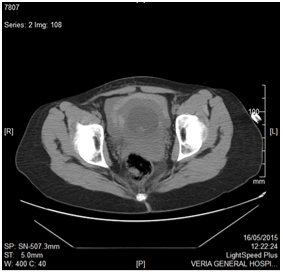

Because of the equivocal findings of the ultrasound an abdominopelvic CT scan with contrast was performed which revealed a large amount of free intraperitoneal fluid and identified with certainty that the source of bleeding was the lower pelvis (Figure 3 & Figure 4).

Figure 3 1CT scan without contrast-pelvic section.